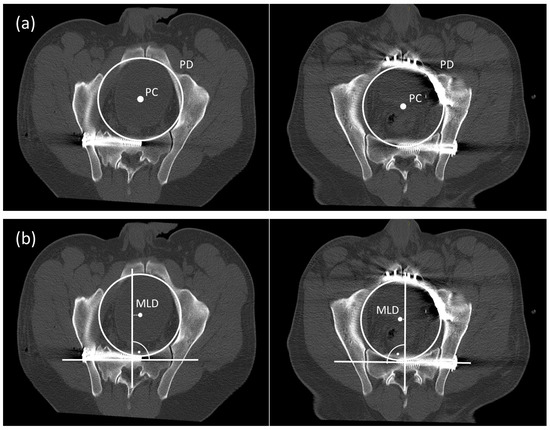

For further 2D measurements two MPR were processed to calculate the pelvic center (PC) and the pelvic diameter (PD) (MPR 1) and the deviation of the pelvic center and the femoral head center (MPR 2). We used the Brainlab viewer Version 5.1.0.97 and OsiriX MD software package (Pixmeo, Bernex, Switzerland) to process these two MPRs.

2.2. Measurements MPR 1

Figure 2 illustrates the exact methods for measurements of the anatomical deformity of the anterior and posterior pelvic ring in MPR 1. MPR1 is a reconstruction at level of the true pelvis marked by a slice cutting through the pelvic brim.

Figure 2.

Measurement PD and PC in a CT scan without anterior stabilization (group A) and with anterior plating (group B) (a). Measurement of the MLD (b).

- -

- Pelvic diameter (PD) and pelvic center (PC): We measured the diameter of the true pelvis as diameter of a circle in MPR 1 (Figure 2a). We defined the center of this circle as Pelvic Center (PC)

- Medio-lateral Deviation (MLD): The sacral axis was determined by drawing a line through the center of the first sacral body parallel to a line through both centers of the pedicle of S1. We measured the distance between the orthogonal line of the sacral axis to the PC (Figure 2b). We defined this distance as medio-lateral deviation (MLD). A positive value indicated a shift of the pelvic center towards the un-injured contralateral side, anegative value expresses a shift towards the side of the SSF.